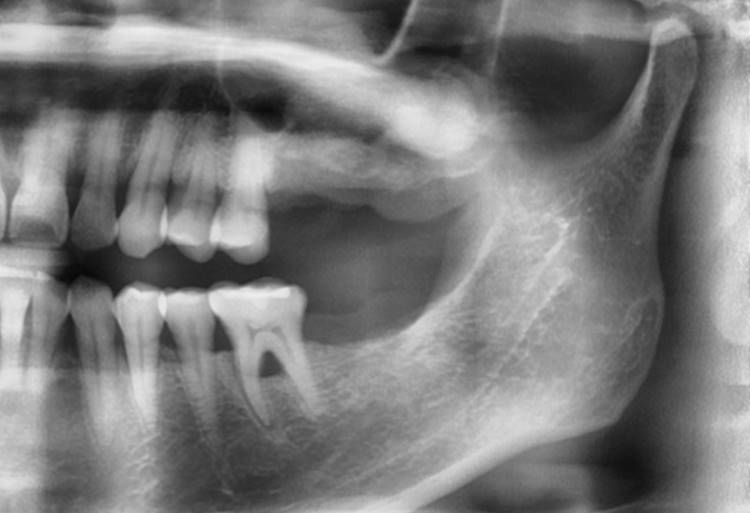

▲Panoramic radiograph before the implant surgery in the lower left area.

▲post-op panoramic radiograph.